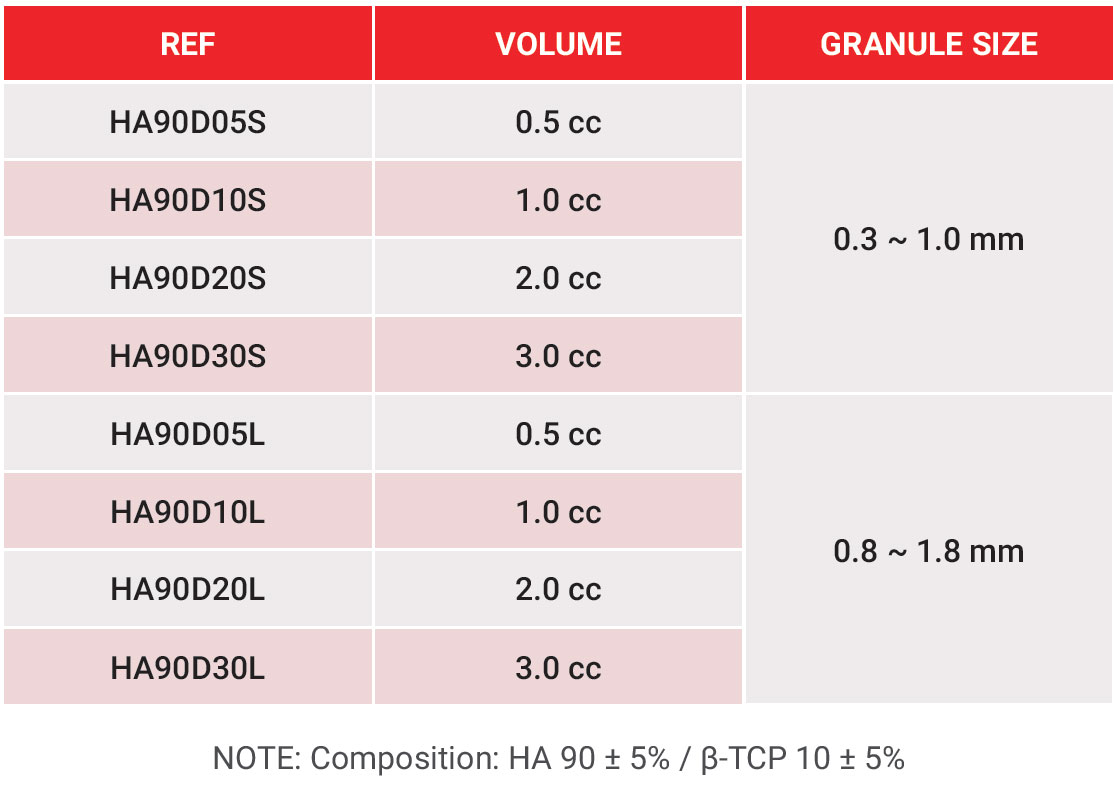

InRoad® Dental Bone Graft should be stored in a dry place at typical temperature and is intended for single use only. InRoad® Dental Bone Graft is available in two (2) sizes: 0.3-1.0mm (small) and 0.8-1.8mm (large). Either size may be purchased in volumes of 0.5cc, 1.0cc, 2.0cc, and 3.0cc.